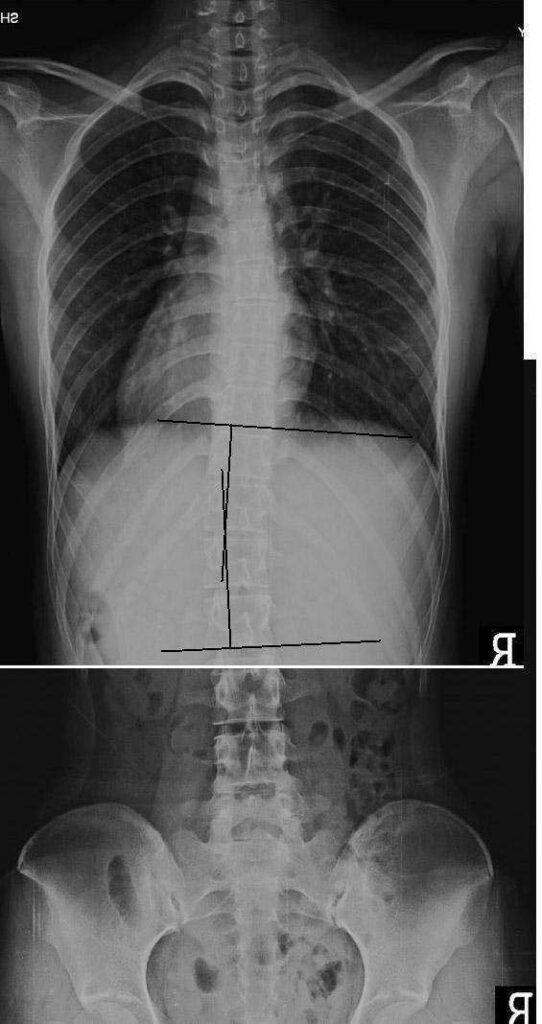

척추 측만증을 추나요법으로 치료한 사례1

분석 : 척추 측만증 치료 전 21도의 측만에서 치료 후 5도의 측만으로 16도 정도의 호전을 보였습니다.

치료 : 주 1회, 3개월간 치료를 받았습니다. 추나요법을 위주로 치료 하였고 체형 교정 운동인 바태운동을 겸하였습니다.

치료 과정에서의 측만각도 호전을 보였으나 현재 완전한 회복을 이룬 것은 아니므로 지속적인 치료가 필요합니다. 본원에서의 치료를 권해 드리며 추나치료 뿐 아니라 바태체형운동을 겸해서 적극적인 치료를 할 계획입니다. 측만 각도의 개선과 더불어 허리 과전만의 감소가 나타나야 합니다.